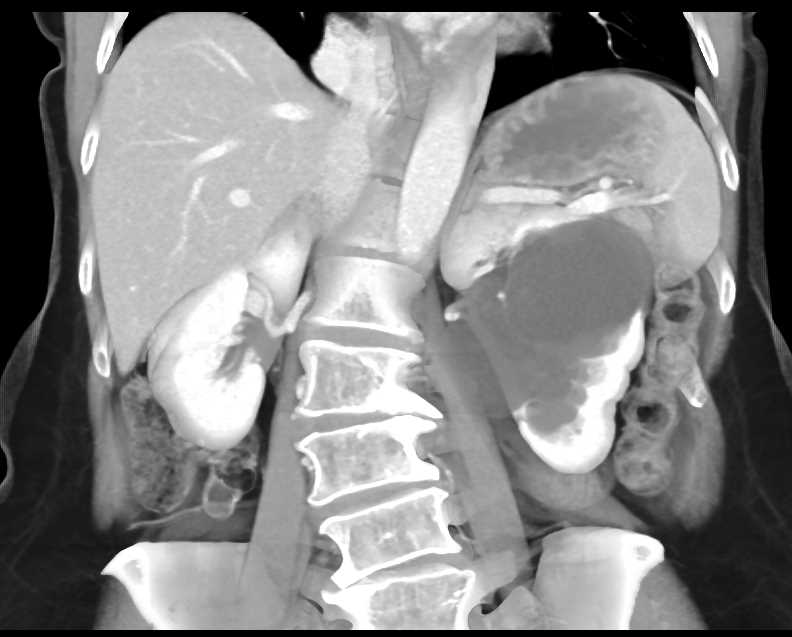

Parapelvic Cysts Left Kidney